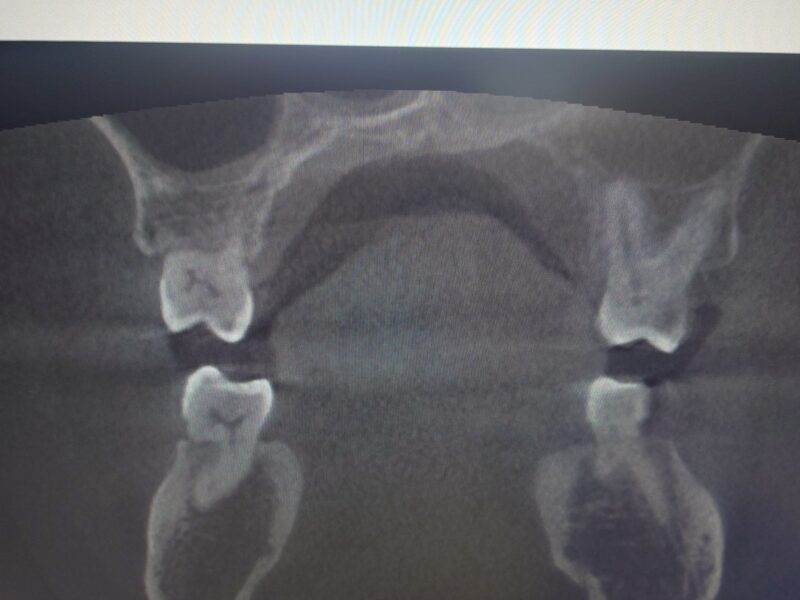

術後 精密根管治療を行ったおかげで 上顎洞内はすっきりしました

患者さんは 長年悩まされてた 鼻づまりが嘘のように治ったと喜んでおられます